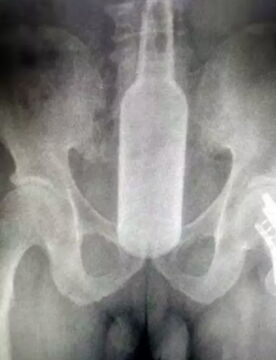

A report from the hospital states that Professor Li Wusheng and his team were unsuccessful in trying to remove the glass by hand as it was lodged 6cm inside his rectum. Uncomfortable X-ray images released show that the glass had completely made itself at home inside Mr Huang.

The man who goes by the name of Mr Huang got the beer 6cm tall glass stuck inside his anus after managing to insert it upside down. Literally bottoms up. The glass which was 5.6cm in diameter managed to get completely wedged in there, leaving surgery as Huang's only option.